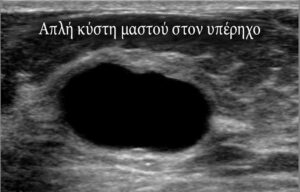

Η απεικόνιση της κύστης στο στήθος γίνεται με υπερηχογράφημα, το οποίο θα βάλει τη διάγνωση και θα κάνει τη διάκριση μεταξύ συμπαγούς ή κυστικής μάζας.

Οι κύστεις του μαστού κατηγοριοποιούνται ως απλές, επιπλεγμένες ή σύνθετες, αναλόγως τα υπερηχογραφικά τους χαρακτηριστικά.

- Η απλή κύστη στο στήθος είναι ένα καλά περιγεγραμμένο ανηχοικό μόρφωμα, δηλαδή εμφανίζεται ως ένα τελείως μαύρο εύρημα στο υπερηχογράφημα με σαφή όρια, χωρίς γκρίζες περιοχές εντός αυτού.